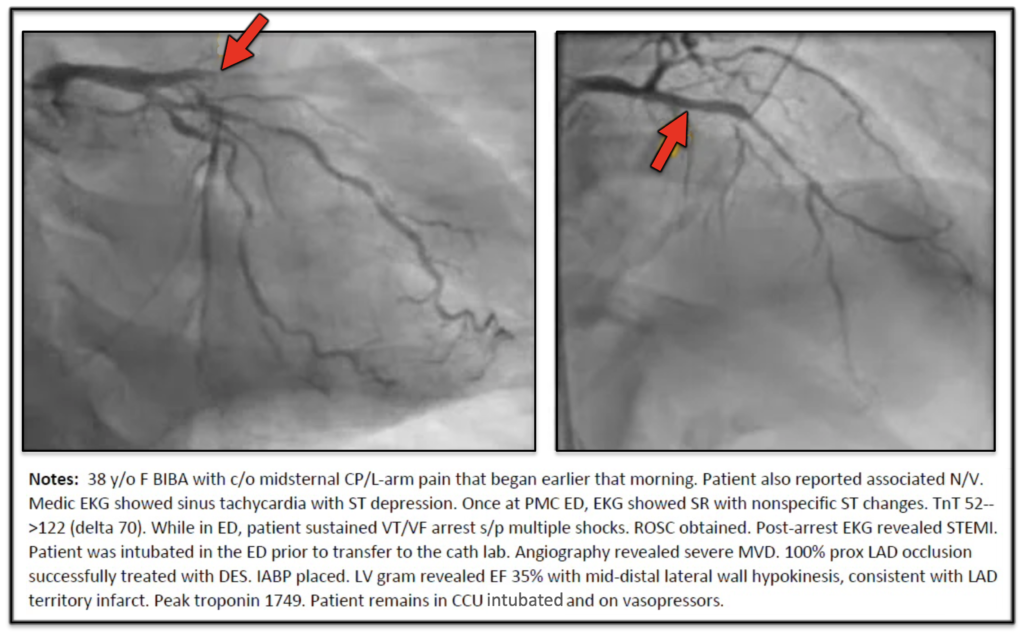

- She went to the cath lab:

So, this unfortunate 30-something woman lost half of her heart, had a cardiac arrest, required a balloon pump and vasopressors — all because no one could read her “Non-STEMI” EKG that was a total coronary occlusion.

- She will probably have permanent heart failure, if she lives.